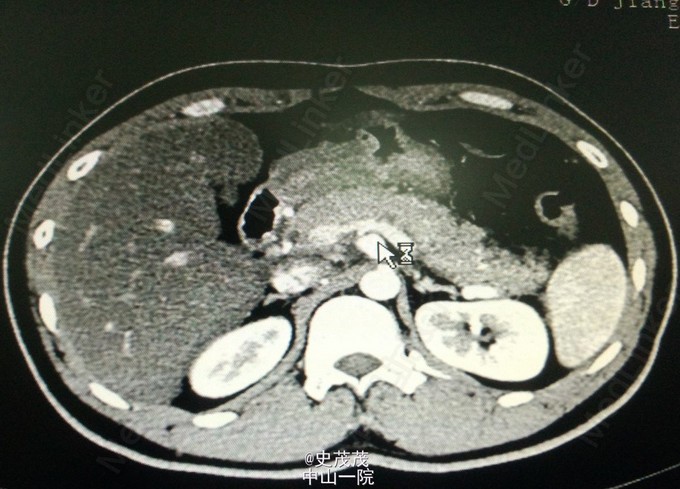

这是一张ct片,发现什么问题了吗?